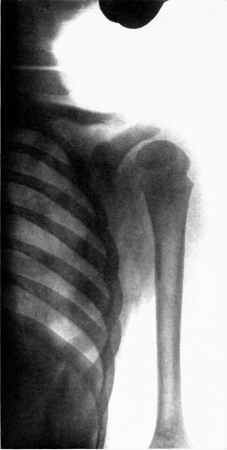

| 16. | Subperiosteal hemorrhage and separation of epiphysis. Roentgenogram | 192 |

| 17. | Periosteal “tags” and “streamers.” Roentgenogram | 193 |